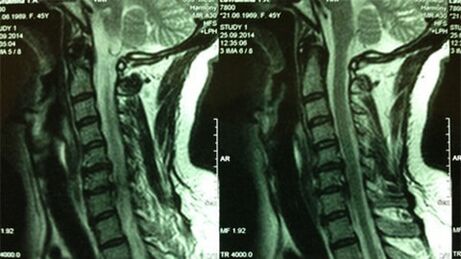

- X -ray of the cervical part;In the initial stage of the process, the MRI of the cervix will have more information - it will ensure the high quality of the solid and soft tissue - will show the condition of the discs, the presence of bone cells, deformed, damage to roots and blood vessels;will assess the status of ligaments, muscles, bone tissue;